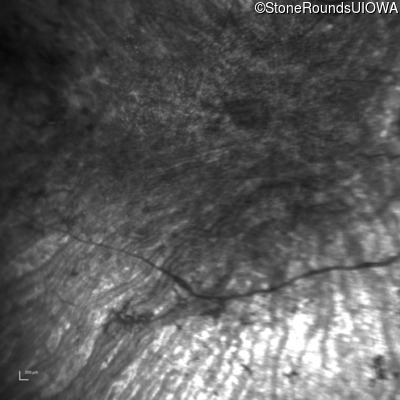

Infrared Fundus Photograph - Left - 5/140 sc

Exemplar